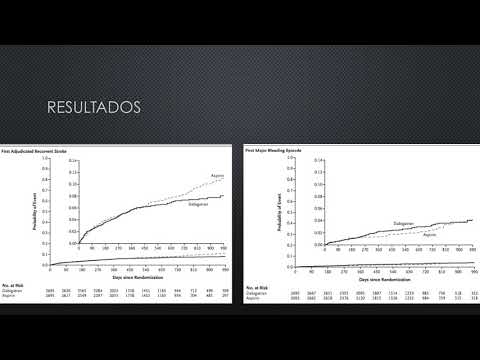

Uso de dabigatrán para la prevención de accidente cerebrovascular después de un accidente cerebrovascular de origen indeterminado. Dra. María Victoria Vannoni. Residencia de Cardiología. Hospital C. Argerich. Buenos Aires